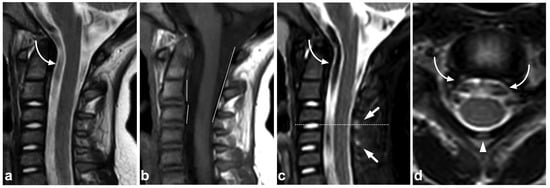

4.3. Anterior and Posterior Longitudinal Ligaments

Anterior and posterior longitudinal (ALL and PLL) injuries occur as part of a gross fracture–dislocation. The literature on the pediatric population’s isolated or non-dislocated ALL or PLL injuries is scarce. These injuries might be rare, especially in younger children [49], but the overall incidence is unknown. Moreover, in our clinical practice, we have found non-dislocated ALL and PLL injuries uncommon. An example of a discrete, partial ALL tear as a part of a non-dislocated flexion–extension cervical spine injury is presented in Figure 10.

Figure 10.

(a) Sagittal T2-weighted. (b) Sagittal STIR. (c) Sagittal STIR, cropped image. (d) Sagittal STIR, cropped right-sided off-midline image. A 17-year-old male, motor vehicle accident. Cervical spine injury at level C6/7 in particular. Compression fractures in the vertebral bodies C7, Th1, and Th3 (asterisks) and right-sided processus articular superior fracture in C7 (black arrowhead). ALL is partly torn at level C6/7 (white arrows), best seen in image (d). Moreover, the intervertebral disc at level C6/7 is edematous and inhomogeneous due to discal injury. Intact ALL is demonstrated at level C7/Th1 (white arrowhead). Soft tissue edema is seen at the prevertebral space, interspinous ligaments, deep posterior cervical muscles, the interspinous ligament, and inside and outside the facet joint (curved arrows). PLL and ligamentum flavum are intact, and no malalignment is seen.

5.2. Muscle Injuries

MRI is the gold standard in the imaging of muscular trauma [54]. Spinal muscle trauma seldom needs any specific treatment. Muscle trauma can best be appreciated on fat-suppressed T2-weighted images, where it appears as areas of high signal (post-traumatic edema) (Figure 12). The hematomas associated with major muscular injuries are also visible in fat-suppressed T2-weighted images.

Figure 12.

(a) Coronal STIR. (b) Sagittal STIR, off-midline right-sided image. (c) Axial T2-weighted, level C6 (dotted line in the image (b)). A 12-year-old male, cervical flexion injury in a trampoline accident. MRI demonstrates right-sided grade 1 muscle injury (white arrows) in the following muscles: rotatores, multifidus cervicis, interspinales, spinalis, and semispinalis. A minor edematous strain of the interspinous ligaments is seen at levels C5/6 and C6/7 (arrowheads).